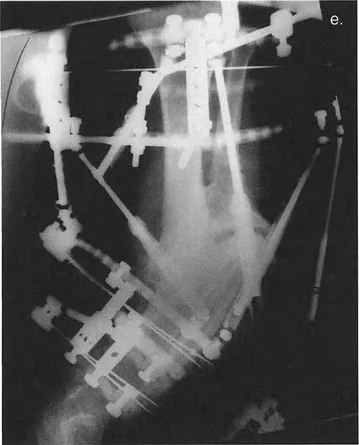

إطار تايلور المكاني وبرمجيات التصميم بمساعدة الحاسوب CAD

لقد أحدث إطار تايلور المكاني (TSF) ثورة في تطبيق مبادئ بالي. يعتمد هذا الإطار على منصة ستيوارت-غوف (Stewart-Gough platform)، وهي آلية روبوتية سداسية الأرجل تُستخدم في محاكيات الطيران. يتكون إطار تايلور المكاني من حلقتين متصلتين بستة دعامات تلسكوبية. يتيح تعديل أطوال هذه الدعامات الستة تصحيحًا متزامنًا لجميع درجات الحرية الست.

يُعد برنامج التصميم بمساعدة الحاسوب (CAD)، الذي طورته شركة Orthocrat Ltd. في الأصل، أداة لا غنى عنها للتحليل التفصيلي والدقيق للتشوه ومعلمات التركيب باستخدام الصور الإشعاعية الرقمية. يتطلب هذا البرنامج من الجراح إدخال ثلاث مجموعات متميزة من البيانات:

- معلمات التشوه: حجم التشوه بستة محاور (على سبيل المثال، 10 درجات تقوس للداخل، 5 درجات تقوس أمامي، 15 ملم تقصير، إلخ).

- معلمات الإطار: حجم الحلقات والأطوال الأولية للدعامات الست.

- معلمات التركيب: كيفية وضع الحلقة المرجعية في الفضاء بالنسبة لقطعة العظم المرجعية (الإزاحات الأمامية الخلفية، الجانبية، والمحورية).